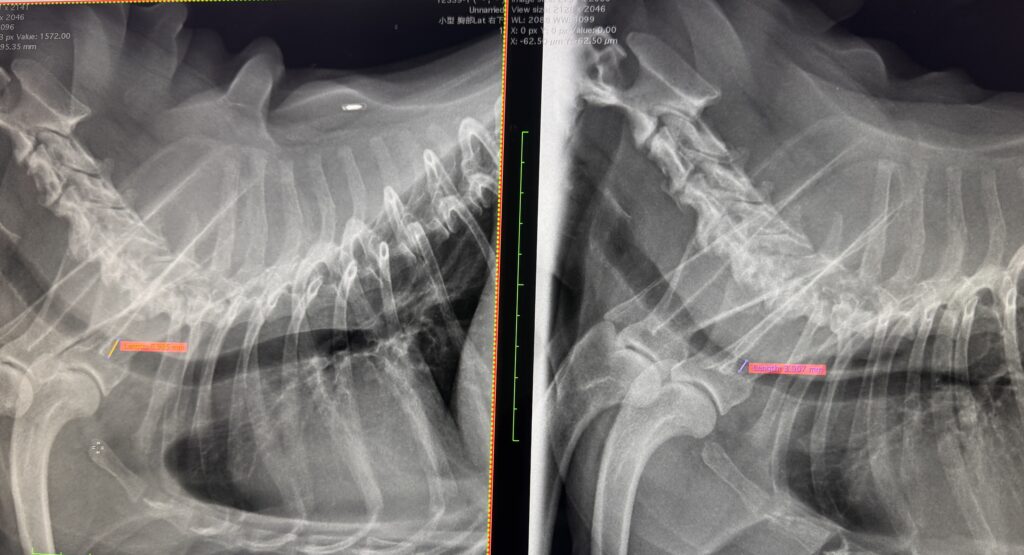

診断名:気管虚脱

呼吸のたびに気管が押しつぶされて狭くなって(写真右)呼吸困難になる病気だそうで。